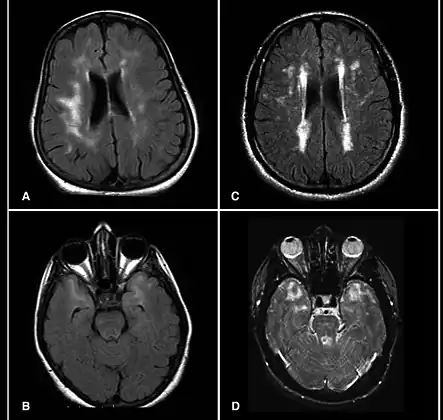

Brain MRI from patients with CADASIL showing multiple lesions.

MRIs show hypointensities on T1-weighted images and hyperintensities on T2-weighted images, usually multiple confluent white matter lesions of various sizes, are characteristic. These lesions are concentrated around the basal ganglia, peri-ventricular white matter, and the pons, and are similar to those seen in Binswanger disease.[2][11] These white matter lesions are also seen in asymptomatic individuals with the mutated gene.[12] While MRI is not used to diagnose CADASIL, it can show the progression of white matter changes even decades before onset of symptoms.